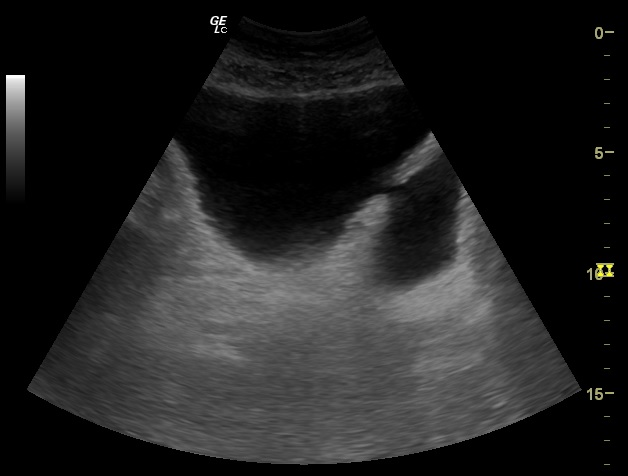

Hallazgos ecográficos

Glándula prostática de 4,28 x 5,81 x 4,57 cm (Figura 1). Volumen prostático: 59,45 ml. Pared de vejiga no engrosada. Se objetiva divertículo vesical (Figura 2) único localizado en pared postero lateral. No se observan lesiones intravesicales ni tampoco en la luz del divertículo (Figura 3). Volumen posmiccional 240 cc.